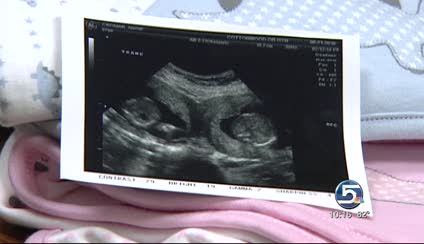

Angie Cromar's first ultrasound revealed something shocking to her and her doctor.

What they saw were two separate babies at slightly different stages of development.

"[He said] I'm five weeks and four days in one, and six weeks and one day in the other," Angie said.